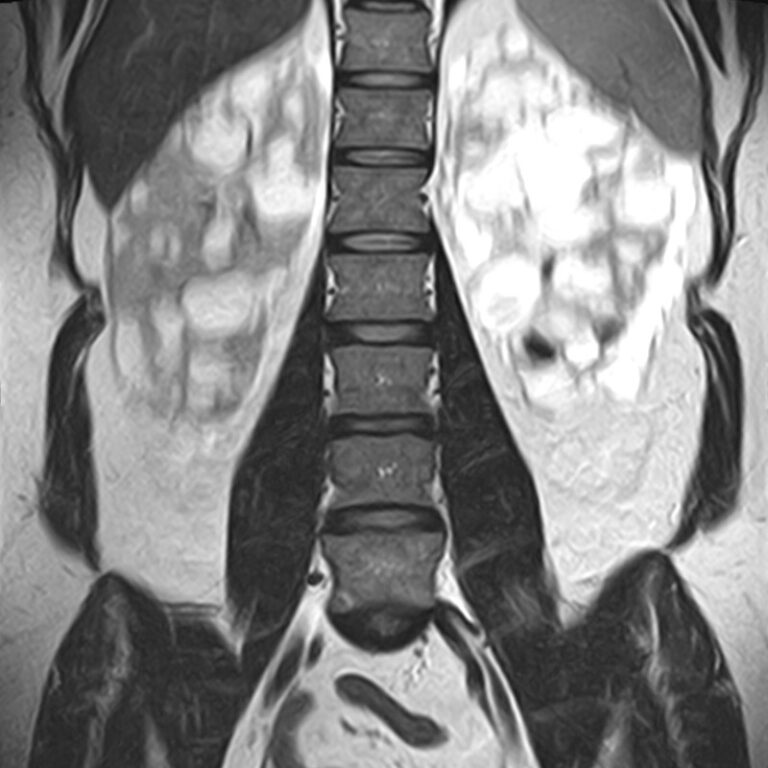

Наиболее точным и эффективным способом диагностики причин появления болей в нижней части спины является МРТ пояснично-крестцового отдела позвоночника. С помощью данного метода можно оценить состояние всех анатомических структур позвоночного столба на исследуемом уровне, безошибочно выявить происхождение болевого синдрома и назначить своевременное лечение.

Многим пациентам интересно, что показывает МРТ пояснично-крестцового отдела. Высокая детальность получаемых с помощью МР-диагностики изображений позволяет с точностью выявить следующие заболевания, локализующиеся в области поясничного отдела позвоночника:

• протрузии и грыжи межпозвонковых дисков;

• дегенеративные заболевания: остеохондроз, спондилез, спондилоартроз;

• последствия перенесенных травм, такие как компрессионные переломы, подвывихи и смещения позвонков;

• новообразования первичного и вторичного генеза;

воспалительные и деструктивные изменения позвонков и окружающих мягких тканей.